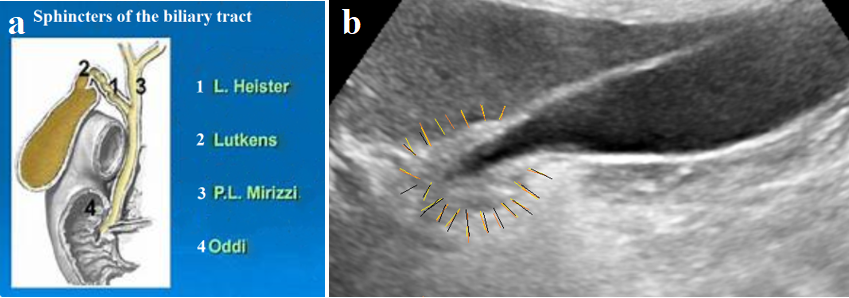

The function of the bile ducts is to store, concentrate, and transport bile from the liver to the duodenum. To perform this function, the extra biliary tract consists of the duct system, the gallbladder, and the bile duct. The sphincter between the gallbladder and the cystic duct (Lutkens' sphincter) contracts after the gallbladder is fully filled. During its contraction, fluid is absorbed and bile concentration increases. After a meal, under the influence of cholecystokinin (CCK), the Lutkens sphincter, as well as SO, relaxes. The gallbladder contracts, and the entire portion of bile enters the duodenum. In addition to the effect of CCK, there is a reflex connection between the gallbladder and the gallbladder sphincter: an increase in pressure in the gallbladder leads to relaxation of the gallbladder sphincter and SO [16]. A peristaltic wave in the common duct conducts a bolus of bile in accordance with the law of the intestine [11]. Proximal to the bolus, the duct contracts, and caudally, the pressure decreases. The final peristaltic wave, near the SO, creates high pressure, which leads to relaxation of the SO, and the bile bolus is injected into the duodenum. In this generally accepted picture, which envisions the gradual and timely execution of each action, there is no room for retrograde peristalsis. In addition to the SO, three more sphincters have been described in the biliary tract, the presence of which has not been confirmed by other studies. However, the gallbladder sphincter (Lutkens' sphincter), whose function is unquestionable, is surprising given how minute its muscle mass can perform such an important physiological role. Figure 4 b shows an example of gallbladder dyskinesia, which manifests as swelling of the gallbladder sphincter.

Figure 4. (a) Schematic diagram of the biliary sphincters described. (b) US gallbladder of a 78-year-old female patient with typical pain in the right hypochondrium and right shoulder, which had never occurred before. History and radiographic examination indicate mild GERD. The pain resolved spontaneously after 3 days while taking PPIs. The thickened wall at the gallbladder outlet, marked with yellow lines, indicates swelling of the gallbladder sphincter.